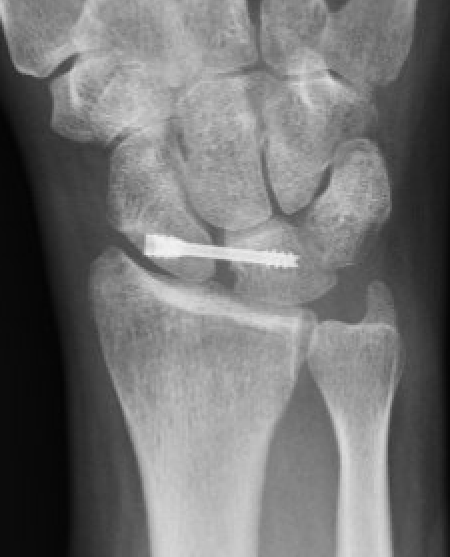

X-ray

Scapholunate gap > 3 mm

AP

| Terry Thomas sign | Cortical ring sign | Scaphoid shortened |

|---|---|---|

|

Increased scapholunate interval > 3 mm compared with other side |

End on view of distal scaphoid due to flexion | Shortened due to flexion |

RASL (Reduction and Association ScaphoLunate)

Technique

Reduce SL joint with K wires

- secondary radial incision

- headless compression SL screw

- ? remove at 3 months

- creates mobile synchondrosis